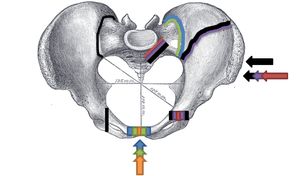

Pelvic fractures are most commonly described using one of two classification systems. The different forces on the pelvis result in different fractures. Sometimes they are determined based on stability or instability.[2]

The Young-Burgess classification system is based on mechanism of injury: anteroposterior compression type I, II and III, lateral compression types I, II and III, and vertical shear,[3] or a combination of forces.

Lateral compression (LC) fractures involve transverse fractures of the pubic rami, either ipsilateral or contralateral to a posterior injury.

The most common force type, lateral compression (LC) forces, from side-impact automobile accidents and pedestrian injuries, can result in an internal rotation.[4] The superior and inferior pubic rami may fracture anteriorly, for example. Injuries from shear forces, like falls from above, can result in disruption of ligaments or bones. When multiple forces occur, it is called combined mechanical injury (CMI).

Open book fracture

One specific kind of pelvic fracture is known as an 'open book' fracture. This is often the result from a heavy impact to the groin (pubis), a common motorcycling accident injury. In this kind of injury, the left and right halves of the pelvis are separated at front and rear, the front opening more than the rear, i.e. like an open book that falls to the ground and splits in the middle. Depending on the severity, this may require surgical reconstruction before rehabilitation.[5] Forces from an anterior or posterior direction, like head-on car accidents, usually cause external rotation of the hemipelvis, an “open-book” injury. Open fractures have increased risk of infection and hemorrhaging from vessel injury, leading to higher mortality.[6]